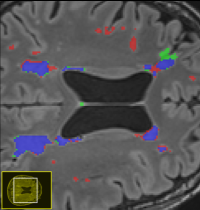

White matter hyperintensities (WMHs) are among the signs of vascular dementia on conventional MRI. In this thesis, relevant automated algorithms for segmentation of WMHs shall be compared for their performance on a clinical cohort.